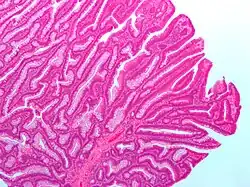

O tipo do tumor é geralmente diagnosticado através da análise de tecido removido através de uma biópsia ou cirurgia. O diagnóstico patológico geralmente contém a descrição histológica do cancro, e o grau. O tipo mais comum de cancro colorretal é adenocarcinoma, que compõe 95% dos casos - acredita-se que a maioria dos casos de cancro colorretal envolvam tumores originários de pólipos adematosos. Outros tipos, mais raros, de cancro colorretal, incluem linfoma e carcinoma espinocelular. As causas do cancro colorretal não são conhecidas com exatidão no presente.

Adenocarcinoma é um tipo de tumor maligno epitelial, que se origina do epitélio glandular da mucosa colorretal. Tal tumor invade a parede, infiltrando a mucosa muscular, a submucosa, e daí, a muscularis propria. As células do tumor abrigam estruturas tubulares irregulares, de estrutura pluristratificada, lúmens múltiplos, e estromas reduzidos. Por vezes, as células do tumor secretam muco, que invade o fluido intersticial, produzindo grandes agrupamentos de muco e colóide (que, visualmente, aparecem como "espaços vazios") - é o chamado adenocarcinoma colóide, pouco diferenciado. Se o muco permanece dentro da célula do tumor, o muco empurra o núcleo celular para a periferia da célula - célula do tipo signet-ring. Dependendo da arquitetura glaudular, pleomorfismo celular, e padrão da secreção de muco, o adenocarcinoma pode ser categorizado em três graus de diferenciação: bem diferenciado, moderadamente diferenciado, e mal diferenciado.[48]